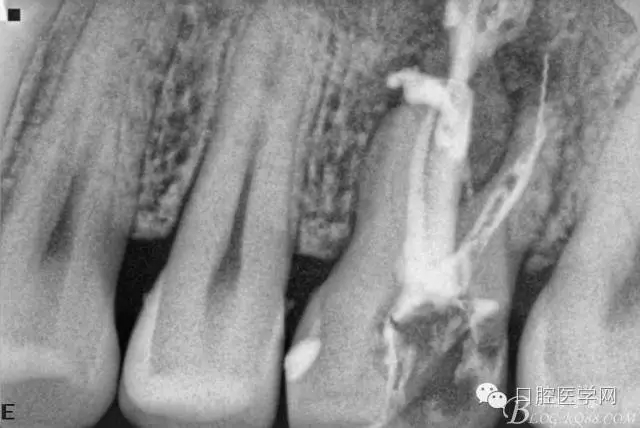

四個月后患牙Ⅰ°松動明顯好轉(zhuǎn),根管內(nèi)無異物,可行根管充填。試主尖片。

根管充填后(遠頰根內(nèi)有一斷針)。